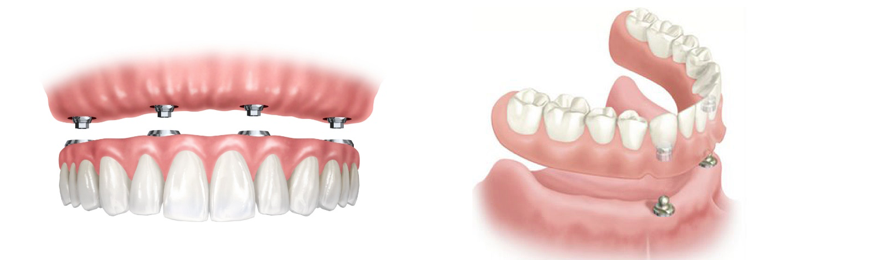

Prótesis fija

Si le faltan todas las piezas dentales, puede elegir una solución permanente mediante la prótesis fija.

¿Cómo lo hacemos? implantamos en el hueso ocho piezas de titanio biocompatibles, que sujetarán las prótesis repartiendo adecuadamente la fuerza de la masticación.

Sobre estos anclajes, fijamos individualmente cada nueva pieza dental. Realizadas en metal y cerámica, las nuevas piezas combinan un aspecto totalmente natural con una mayor resistencia y durabilidad.

El resultado es lo más parecido a volver a disfrutar de su propia dentadura.

Sobredentadura

El modelo de sobredentadura para prótesis completas es una solución que le aporta seguridad de forma sencilla.

Se distribuye a lo largo de la encía cuatro implantes dentales de titanio biocompatible, que simulan la función de las raíces dentales asegurando la dentadura al hueso.

Sobre estas “nuevas raíces”, fijamos una estructura metálica en la que se encaja mediante abrazaderas la prótesis completa.

Así usted contará con la tranquilidad y la estética de una dentadura fija, y además la libertad de extraer, recolocar y limpiar su prótesis con facilidad.